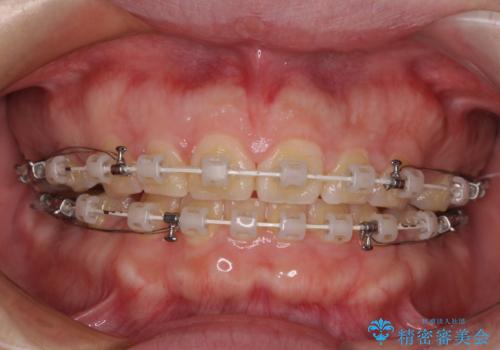

- 矯正装置

- 審美装置

- 2年6ヶ月

- 10-30回